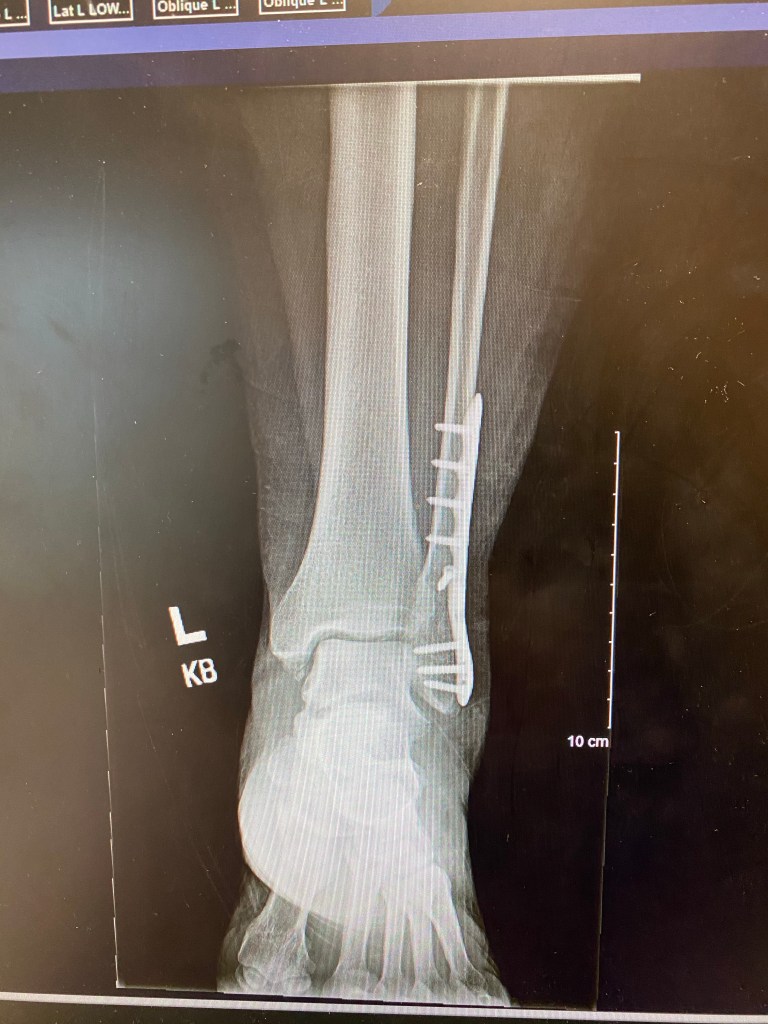

So that bring me to the current state of the ankle. I hobbled into my 6 week post op visit just one week ago with my boot and crutches. Anxiously awaiting the new X-ray results and the doctors game plan.

I was shocked when the dr came in pulled up the X-ray and told me the bone was healed back in place and I could begin fully weight bearing right away. I think it was a surprise to me and I wondered how does one go from one extreme to the other with a simple picture of an X-ray. I was of course shocked for 20 seconds and then immediately joy filled.

The doctor explained that because I was active that the joint was mobile and it would be great for me to wear my sneakers and begin strengthening the ankle. I still had one scab on the incision which is normal. Even now at 7 weeks post op there’s one scab that’s being super stubborn.